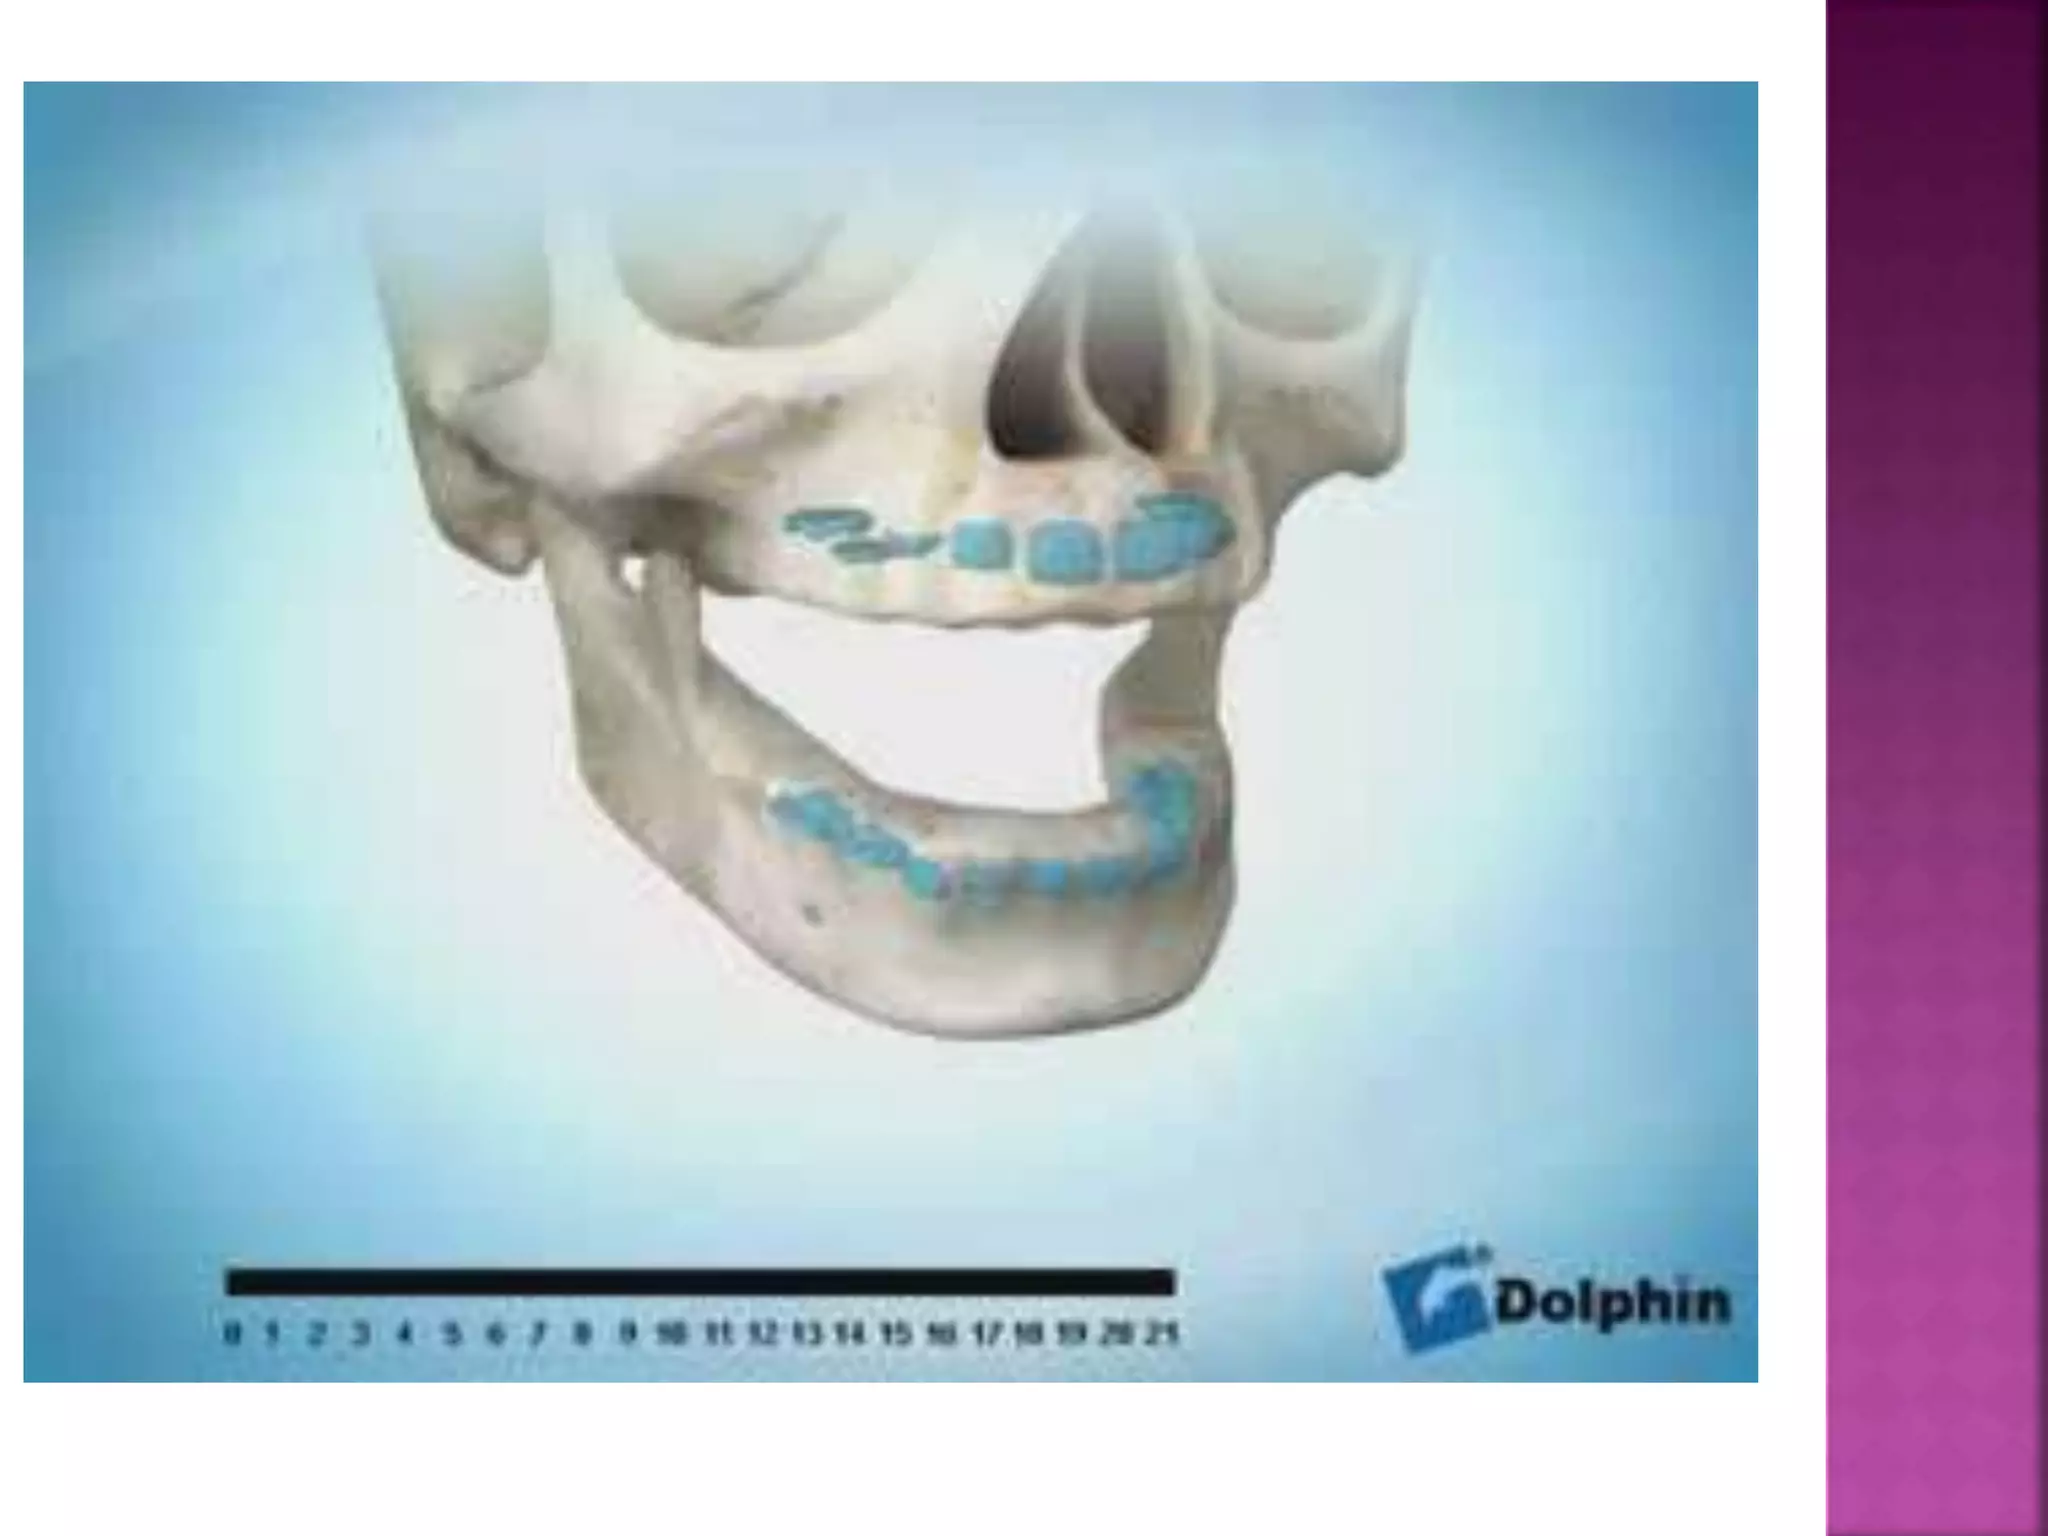

 Muscles that elevate the mandible:

The masseter : elevation and retraction of

mandible.

The temporalis : elevation and retraction of

The medial pterygoid : elevates mandible, closes

jaw, helps lateral pterygoids in moving the jaw

from side to side.

 Muscle that depress the mandible:

The lateral pterygoid : depresses mandible

Three of the muscles of mastcation (temporalis , masseter and

medial pterygoid ) support the mandible against gravity and the

action of the submandibular muscles . The former exert an upward

pull and the latter downward pull.

Masseter

Temporalis

Medial PterygoidThe masseter attaches superiorly to the medial and inferior aspect of the zygomatic arch and inferiorly to the lower border

on the lateral surface of the ramus of the mandible.

The temporalis attaches superiorly to the floor of the temporal fossa to the fascia that overlies it. Inferiorly it attaches to the

coronoid process and to the anterior surface of the ramus.

The medial pterygoid runs from the medial surface of the lateral pterygoid plate and the palatine bone to the lower edge of

the medial surface of the ramus of the mandible.

The lateral pterygoid attaches to the lateral surface of the lateral pterygoid plate and the greater wing of the sphenoid bone.

It runs to the pterygoid fovea at the neck of the mandible and the capsule of the temperomandibular joint.

Lateral

Pterygoid